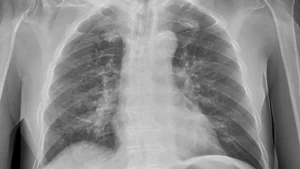

De los tipos de cáncer de pulmón, la OMS señala que los tipos más comunes de cáncer de pulmón son el carcinoma no microcrítico (NSCLC) y el carcinoma microcrítico (SCLC):

“El NSCLC es más común y crece lentamente, mientras que el SCLC es menos común, pero suele crecer rápidamente”.

¿Cuál es el tratamiento contra cáncer de pulmón?

El tratamiento del cáncer de pulmón depende del tipo de cáncer, de su propagación y de la historia clínica de la persona. La detección precoz puede permitir mejores tratamientos y mejores resultados.

Un diagnóstico temprano tendrá mayores posibilidades de tratarse eficazmente y de poder curarse:

“Este tipo de cáncer puede comenzar en las células que envuelven los bronquios, los bronquiolos y/o los alvéolos”.